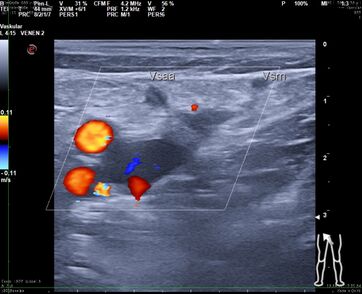

Das Herausreißen der Vene mit dem Stripper ist ein blindes Verfahren, bei dem der Operateur keine Kontrolle darüber hat, wo der Stripper nach Einführen in die Vene entlangläuft. Mehr als 50% der Bevölkerung haben eine Doppelanlage der Vena saphena magna.

Wenn dies nicht durch eine gründliche präoperative Ultraschalluntersuchung durch den Operateur selbst nachgewiesen wurde, wird nur ein Ast gestrippt, durch den verbliebenen zweiten entstehen frühzeitig Rezidivvarizen.

Der akzessorische zweite Saphenaast kann wie die normale Saphena in der gleichen Faszienduplikatur verlaufen, in einer zweiten oder subkutan. Dann wird bei einer Operation durch in der Gefäßanatomie unerfahrene Chirurgen und insuffizienter präoperativer Sonographie der akzessorische subkutane Ast von dem als tiefe Vene fehlgedeuteten intrafaszialen Saphenahauptstamm abgesetzt und gestrippt. Beschwerden und Varizen am Unterschenkel bleiben dann bestehen. Dies ist der häufigste Fehler bei der offenen Krampfaderoperation .